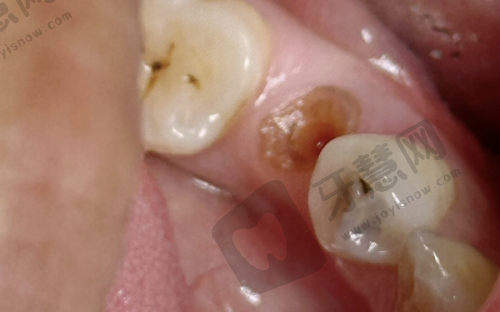

特色项目众多。北京欢乐英辰口腔门诊部拥有多个特色项目。在牙齿正畸项目方面,采用精良的隐形正畸技术,这种技术使用的隐形牙套几乎完全隐形,不影响患者的美观和社交,而且牙套可以自行摘戴,方便患者清洁口腔,减少了牙齿脱矿、龋坏等问题的发生。同时,医生会根据患者的牙齿移动情况,精细调整牙套的力度和方向,确保正畸成效更加理想。种植牙项目,门诊部引进了国内外精良的种植系统,种植过程中,医生凭借不错的技术,能够精细植入种植体,缩短手术时间,减少患者的痛苦。种植体与牙槽骨的结合紧密,稳定性高,使用寿命长,能够为患者修复良好的咀嚼功能。牙齿美白项目,采用安心有效的美白技术,美白剂对牙齿的刺激性小,能够在短时间内让牙齿变得洁白亮丽,而且美白成效持久,让患者拥有自信的笑容。